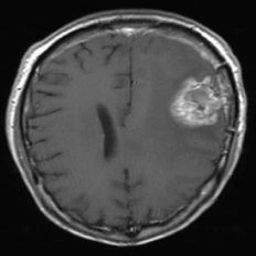

Figure 1: Heatmap Comparison of Unhealthy Images. Different columns show unhealthy MRI images of different positions, sizes, and textures. The first row is the raw image. The second row is the heatmap predicted with PatchCore. The third raw is the heatmap predicted with the proposed method.